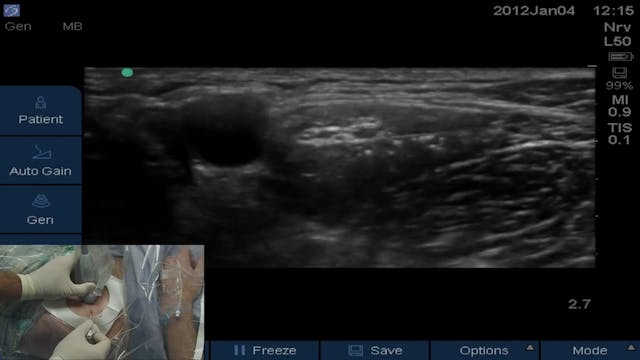

Dr. Stuart Grant, Professor of Anesthesiology at Duke University, describes the anatomy, equipment and technique for the successful placement of an ultrasound-guided femoral nerve block.